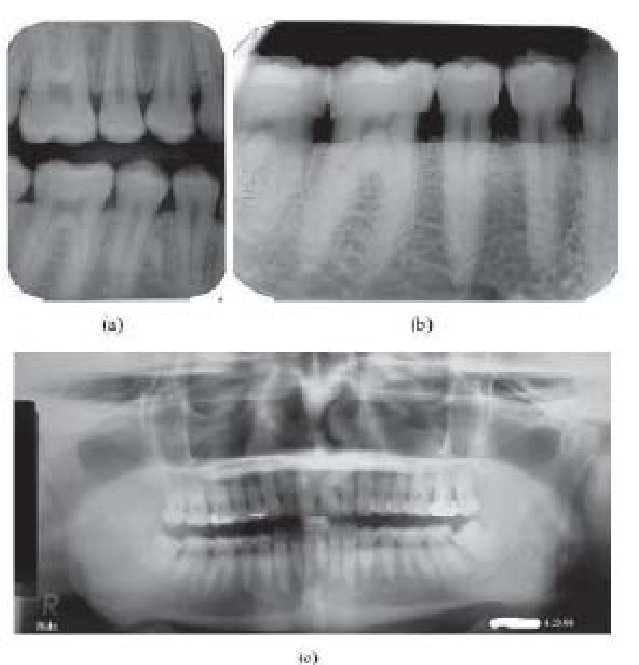

तसेच हल्ली फिल्म ऐवजी सेंसर चे आधुनिक तंत्रज्ञान दातांच्या एक्स रे काढण्यासाठी वापरले जाते. ज्यामुळे लगेच कॉम्प्युटरच्या स्क्रीनवर एक्स-रे दिसतो व फिल्म धुण्याची कटकट वाचते.

सामान्यतः क्लिनिक मध्ये असणारे मशीन व सेंसर हे इंट्रा ओरल एक्स-रे घेणारे असतात ज्यात फिल्म किंवा सेंसर हे पेशंटच्या तोंडात ठेवून काही ठराविक दातांचा एक एक्स रे निघतो.

एक्स्ट्रा ओरल म्हणजे दातांचा बाहेरून जबड्याचा फोटो घेणाऱ्या एक्स-रे घेणाऱ्या मशीन सही उपलब्ध आहे त्यांच्याबद्दल पुढील भागात….